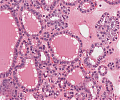

A92 Follikuläres Adenom der Schilddrüse

Randlicher Anteil mit mikrfollikulärem Aufbau (hohe Vergrößerung)

A92 Follikuläres Adenom der Schilddrüse

Randlicher Anteil mit mikrfollikulärem Aufbau (geringe Vergrößerung)

Follikuläres_Adenom1_SD_A92.png

Neoplastische Follikel unterschiedlicher Größe von isomorphen Follikelepithelien mit sog. Resorptionsvakuolen begrenzt

Follikuläres_Adenom_SD_A92.png

Follikulär gebaute Neoplasie mit gemischt mikro und normo-follikulärem Aufbau, umgeben von einer bindegewebigen Pseudokapsel.